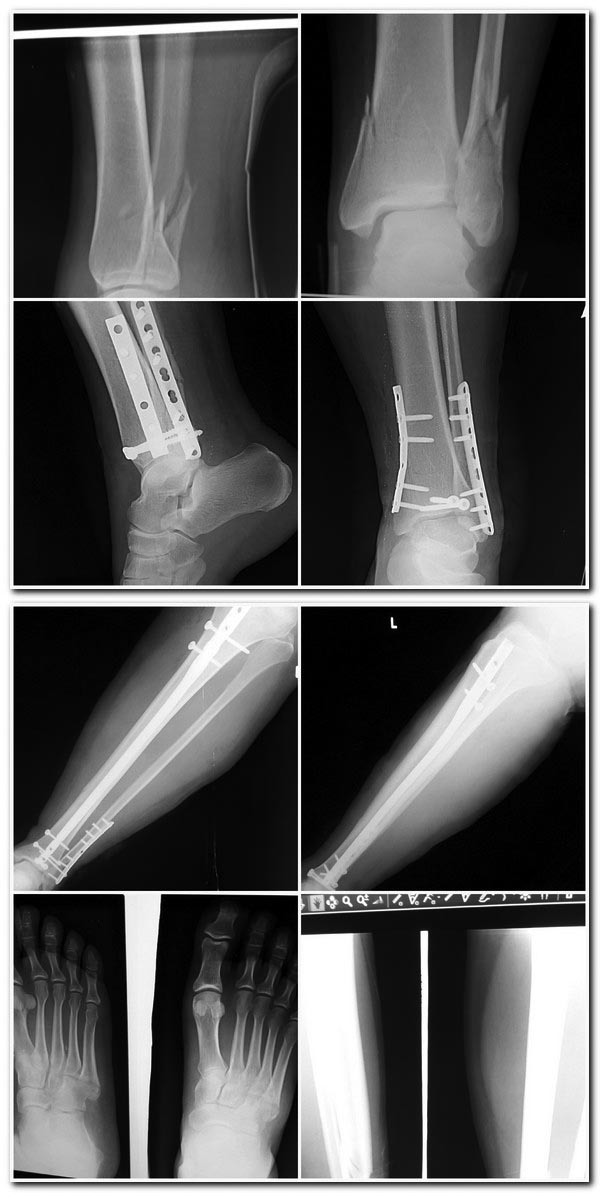

В какие сроки можно нагружать г/стопный сустав у этих больных. Больные

до 50 лет, комплаэнтные. Нужна иммобилизация у них? Что можно почитать

на тему сроков нагрузок на г/стопный сустав после операций на голени?